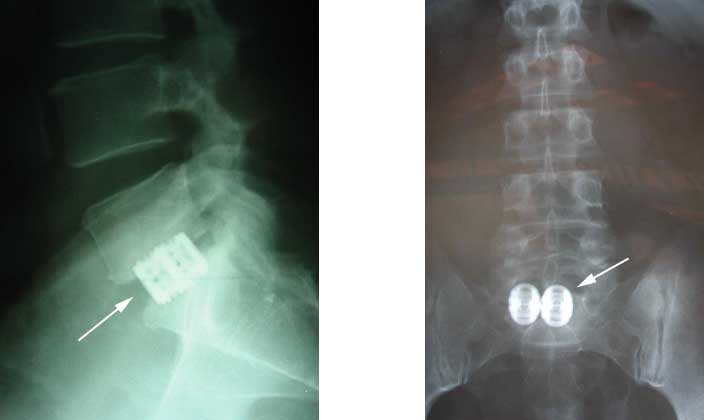

In the lumbar spine, vertebrae can be fused by going through the abdomen [ie, removing the disc and placing bone by opening the belly from the front!]. Figure below shows a anterior [front] fusion with cages only.